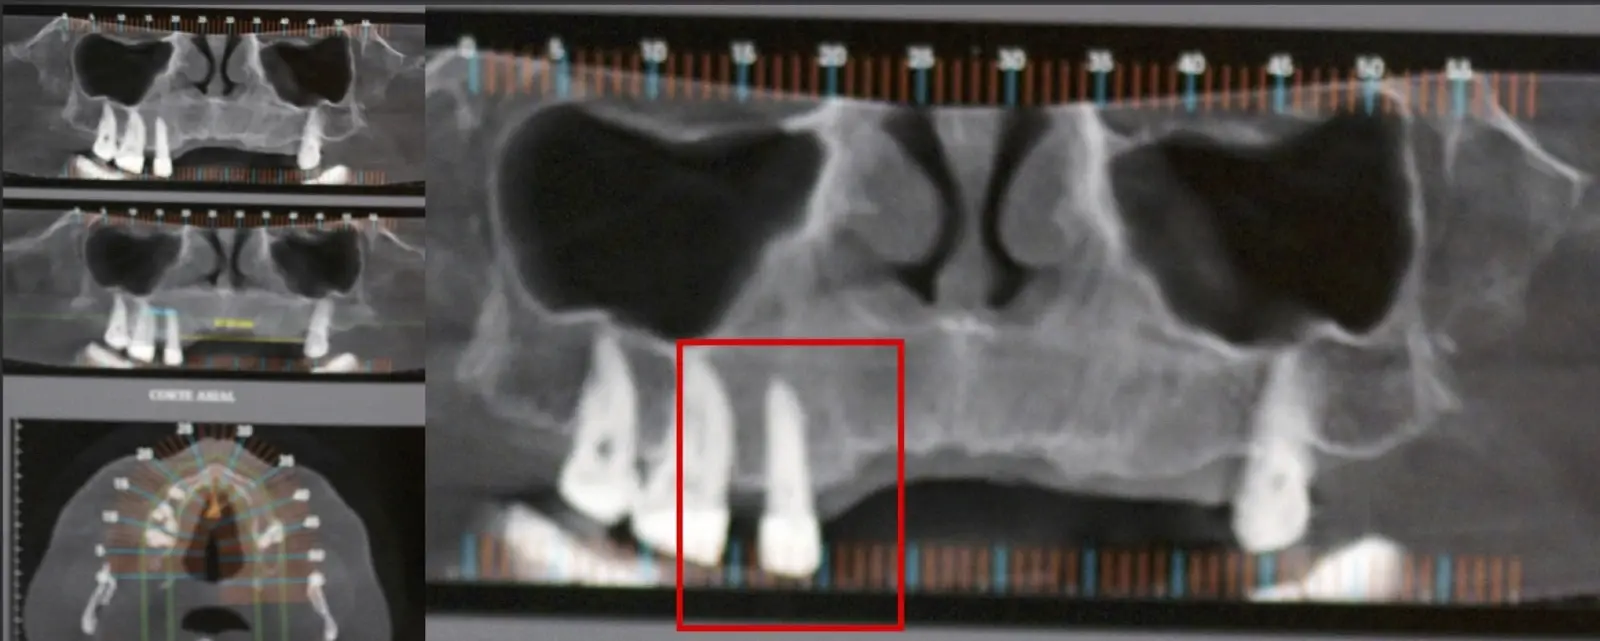

Paciente de sexo femenino de 46 años, llega a la consulta por presentar odontalgia en la pieza 2.1. Al examen clínico se observa restauración coronaria con ausencia de movilidad dentaria y la paciente refiere dolor a la percusión vertical. En la evaluación tomográfica se observó tratamiento de conducto radicular y espigo intrarradicular acompañado de imagen hipodensa a nivel apical compatible con proceso infeccioso crónico. Se procede a realizar apicectomía mediante técnica por desgaste, finalizando con la preparación y obturación de conducto radicular apical por vía retrógrada.

Figura 12. Fotografía frontal: restauraciones cerámicas definitivas, con ausencia de lesiones fistulosas (a). Corte sagital de TCCB pieza 2.1: imagen hipodensa compatible con lesión periapical osteolítica de aproximadamente 5.73 cm de diámetro, con compromiso de la tabla vestibular y palatina (b).